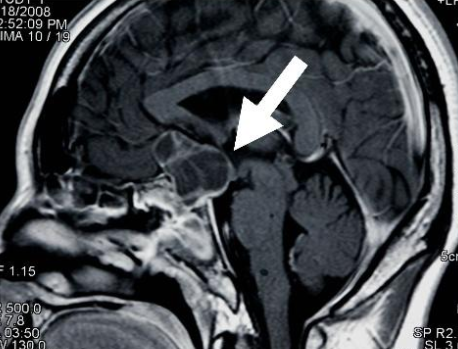

颅咽管瘤起源于脑垂体附近,随着颅咽管瘤的缓慢生长,它会影响脑垂体和脑内其他邻近结构的功能。

颅咽管瘤是脑内常见的先天性肿瘤,通常是囊性的。囊性颅咽管瘤在组织学上是良性的,符合WHO I级,对组织压迫更小,通常不会危及生命。囊性颅咽管瘤手术切除一般认为是较合适的治疗手段,一般脑内良性病变在可以手术切除的情况下被认为是可以治愈的。但颅咽管瘤不手术,吃药可以治愈吗?诸如“放射治疗”、“抽囊液”、甚至“祖传秘方”等不开刀的治疗方法可以治愈吗?非手术治疗效果又如何呢?